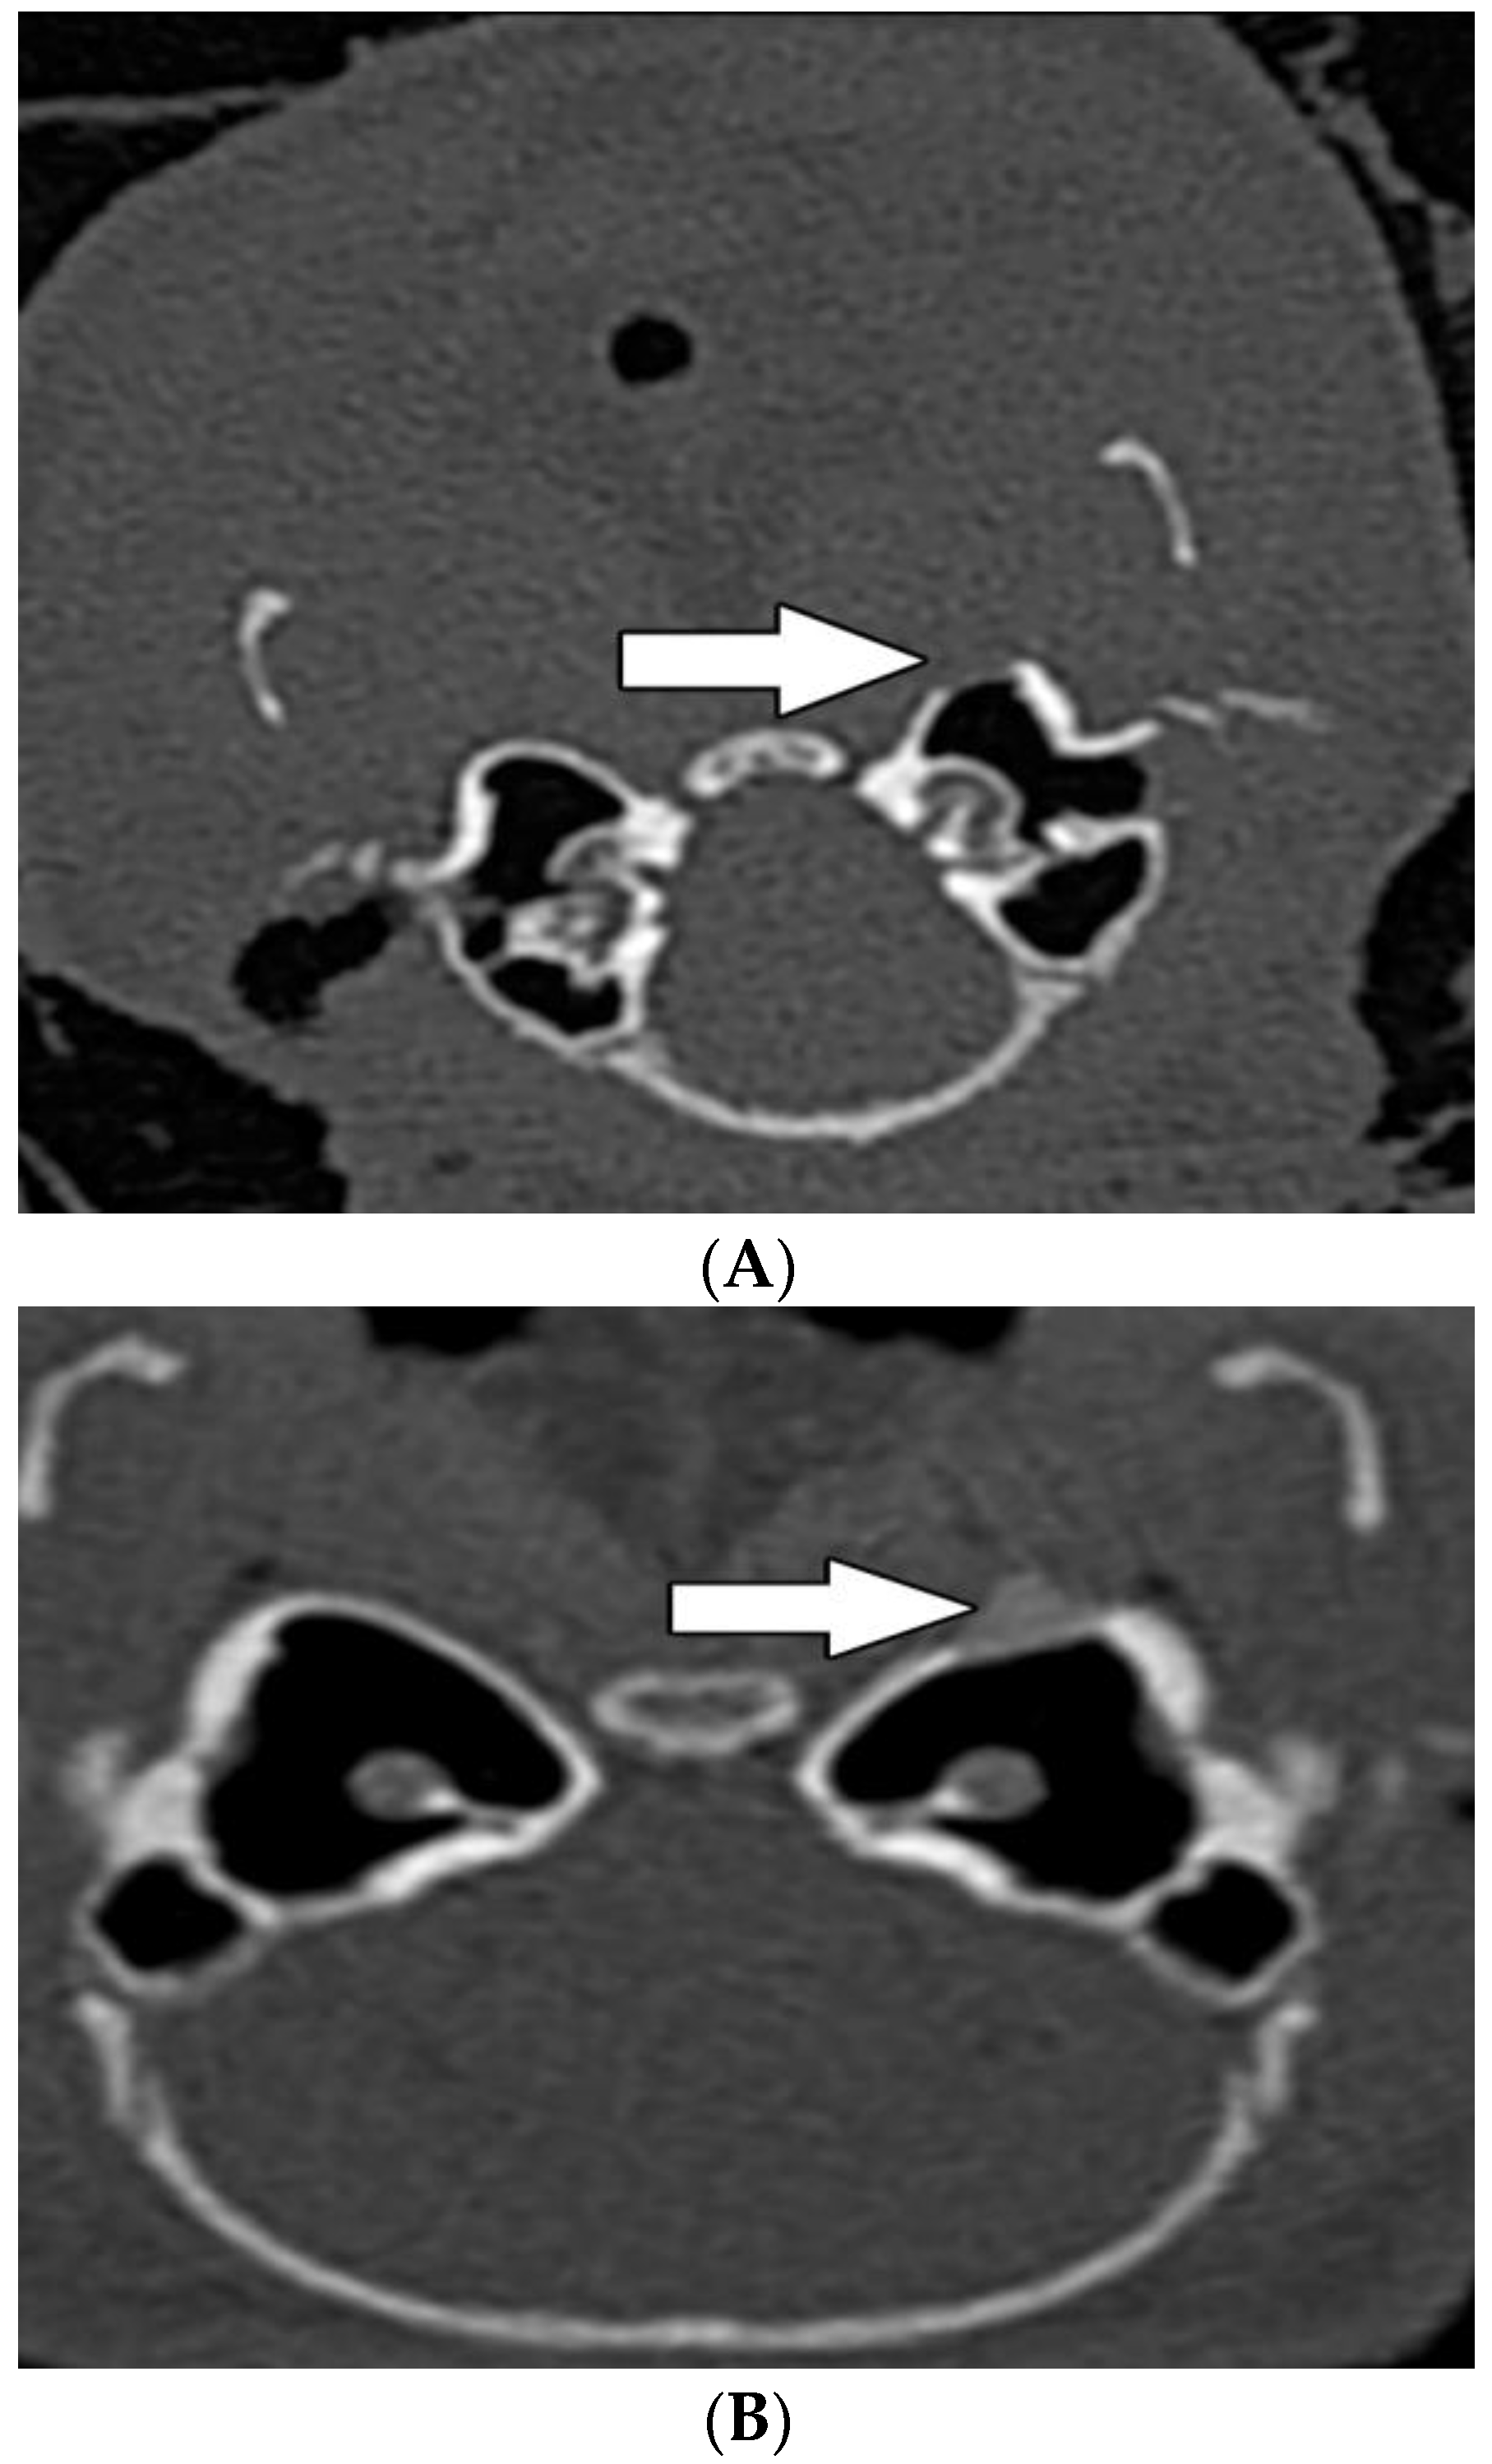

3.3. Radiological Evaluation

| Areal density (HU) | 394 (SEM ± 73) | 1473 (SEM ± 146) | p = 0.00001 |

| Hot spot density (HU) | 958 (SEM ± 126) | 1643 (SEM ± 119) | p = 0.00276 |

| Mucosal thickening | 3 | 1 | p = 0.576 |